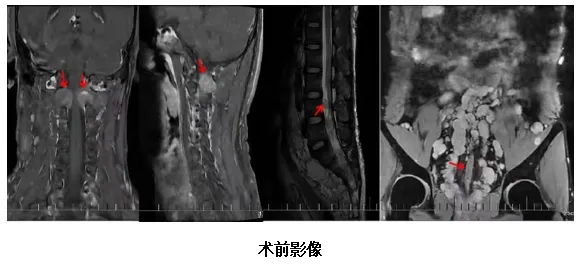

王大姐,今年41岁,因四肢麻木、无力两月余,并加重7天来我科就诊。通过查体发现王大姐双上肢腱反射消失,双下肢腱反射活跃,双上肢体肌力5-级,右下肢肌力4+级,左下肢肌力5-级,双侧Babinski征阳性,侧肘关节以下痛触觉减退,双侧膝关节以下(腓侧重于胫侧)痛触觉减退,深感觉粗侧正常。(可疑T4平面以下痛触觉减退),双侧指鼻试验、跟膝胫试验阳性,宽基底步态,闭目难立征检查不配合,脑膜刺激征(-);当天复查颈椎平扫MR结果示::颈1-胸2椎体层面脊髓占位性病变,考虑室管膜瘤可能。肌电图的结果:EMG:被检部分肌见纤颤正尖波,轻收缩个别被检肌见MUP 偏宽大,重收缩偏弱。NCV: 被检运动和感觉神经传导速度和波幅正常范围。运动神经F波潜伏期正常范围、双侧胫神经 H反射正常范围。提示:神经源性损害肌电改变,累及右侧C5-T1和左侧C5-C7支配肌,脊髓前角细胞或根性损害。为避免肿瘤进展影响后期的生活质量,王大姐 及家属非常信任欧阳一彬主任团队为王大姐进行手术。手术方式:全麻下行高位颈髓多节段髓内肿瘤切除+椎管重建手术。手术过程顺利,达到良好的治疗预期。